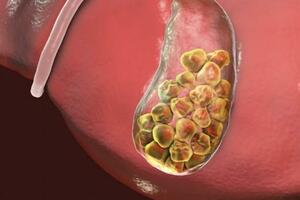

據統計,有超過60多種疾病與濕氣有關。如肥胖、水腫、腹脹、濕疹、皮炎、痤瘡、泌尿系統感染、女性白帶增多瘙癢等。

最嚴重的是:濕氣可能引起頑固性肥胖,這種肥胖引發一系列的疾病,如高血壓,高血脂,甚至會引發惡性腫瘤,身上的腫瘤切了又長,長了又切。因此,去除體內濕氣,刻不容緩!